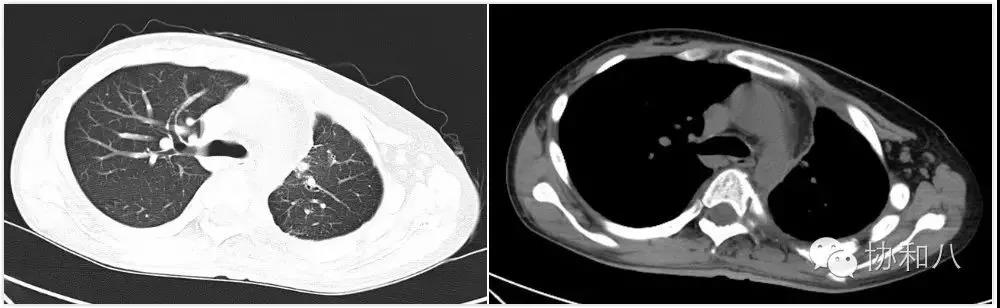

胸部 CT+肋骨重建:胸膜弥漫性增厚伴多发结节,肋骨骨膜反应明显,胸膜间皮瘤可能,脊柱侧弯。

两周后激素减量,体温再次升高,胸背痛加重,复查炎症指标再次升高。复查胸部 CT:胸膜较前有所增厚。

与患者及家属充分沟通,在介入科协助下再行胸膜活检,最终获得了病理诊断。